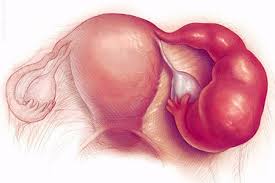

قیمت: 96٬000 تومان - دسته بندی فایل: تحقیق

قیمت: 96٬000 تومان - دسته بندی فایل: تحقیقپاورپوینت بیماری های تناسلی مردان و زنان (ppt) 106 اسلاید

فروش ویژه پاورپوینت حرفه ای بیماری های تناسلی مردان و زنان / تعداد اسلاید: 106 اسلاید